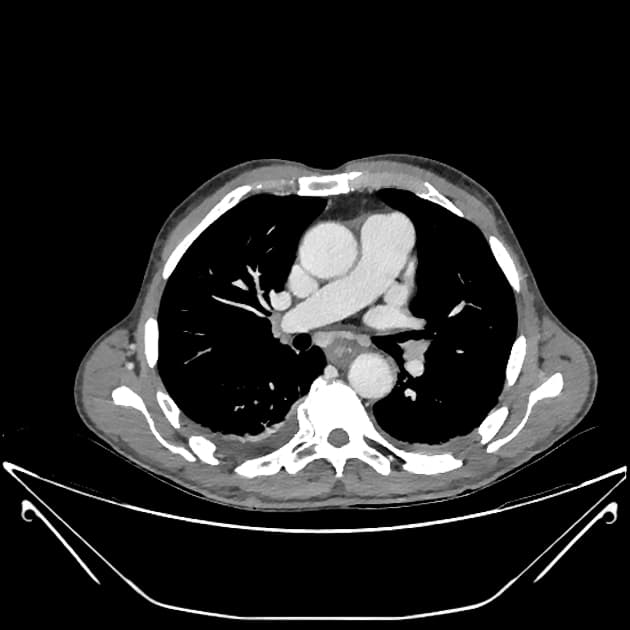

Chụp CT có tiêm thuốc cản quang (pha tĩnh mạch cửa) cho thấy các hình ảnh sau:

Chụp CT (pha động mạch)

Có tắc hoàn toàn thân chính đoạn xa của động mạch mạc treo tràng trên và các nhánh của nó, ngoại trừ các nhánh ruột non gần bên trái và động mạch đại tràng giữa bên phải. Các nhánh ruột non xa, nhánh hồi tràng, động mạch hồi – đại tràng và động mạch đại tràng phải đều bị tắc.

Trong chụp CT đơn pha thông thường ở pha tĩnh mạch cửa, việc chẩn đoán sẽ ngày càng khó khăn hơn vì mức độ tăng quang của động mạch sẽ không rõ ràng.